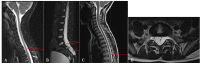

Intracranial hypotension syndrome (IHS) is attributed to reduced cerebrospinal fluid (CSF) pressure. It may be spontaneous or secondary to a history of trauma or systemic disease. We present the case of an 11-year-old boy, with medical history of Marfan syndrome, with orthostatic headache and persistent vomiting (12 hours) following a fall on the sacrococcygeal region. Magnetic resonance showed extradural fluid collections at dorsal and lumbosacral levels, compatible with CSF leak. The condition was resolved with treatment, but the patient had two new episodes during the follow-up period. Thus, an epidural blood patch was performed two years after the first episode. Although HIS is uncommon in children, it should be suspected in patients with orthostatic headache, particularly if the patient presents a connectivopathy. Few studies have assessed the management of HIS in paediatric age. The case presented here and the reviewed available literature provides further data for these type of cases.

Presentamos el caso de un niño de 11 años con cefalea ortostática y vómitos de 12 horas de evolución tras una caída sobre región sacrocoxígea; antecedente de síndrome de Marfan. La resonancia craneomedular mostró colecciones líquidas extradurales a nivel dorsal y lumbosacro compatibles con fístula de LCR. El cuadro se resolvió tras tratamiento, pero hubo dos nuevos episodios durante el seguimiento, por lo que se aplicó un parche hemático epidural a los dos años del inicio.